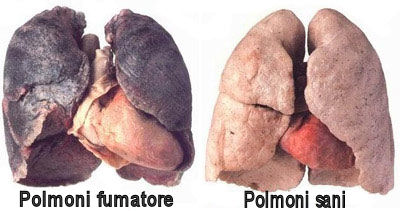

- Come sono i polmoni di un fumatore e quelli di un non fumatore?

MA COSA CI RESTA REALMENTE DENTRO I POLMONI E ALL'INTERNO DEL NOSTRO CORPO?

Il video seguente ci illustra con un piccolo esperimento quanto catrame entra nel nostro corpo e nei nostri polmoni solo dopo il consumo di 400 sigarette, che per un fumatore sono una sciocchezza!